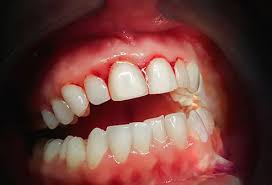

gingivitis

Definition: Inflammatory response resulting from the biofilm accumulation located below the gingival margin

two types: dental biofilm-induced or non-dental biofilm-induced

gingival health: <10%, localized gingivitis: 10%-30%, and generalized gingivitis: >30%

JE at CEJ; 3mm or greater; reversible